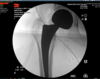

Displaced right femoral neck fracture

- bipolar hemiarthroplasty vs total hip

- Cemented vs Non-cemented

- Anterior approach with fluroscopy afterhours

Supine position with Fluroscopy

Press fit decision